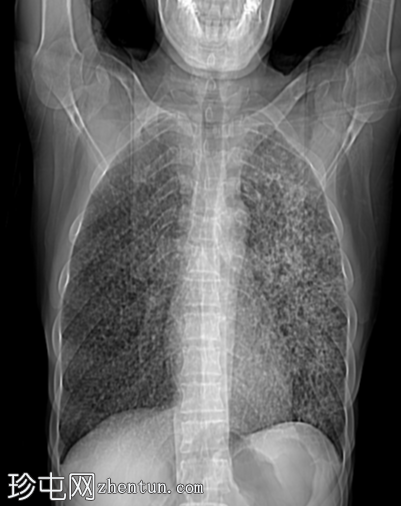

CT扫描图像:双侧肺部广泛粟粒性结节。

双侧肺部广泛粟粒性结节及树芽征,伴左上叶空洞及小气腔实变。

粟粒性疾病是由血源性播散至肺部和其他器官所致,其特征是多个2-3毫米的小结节,随机分布。小叶间隔增厚和细小的小叶内网络通常较为明显。